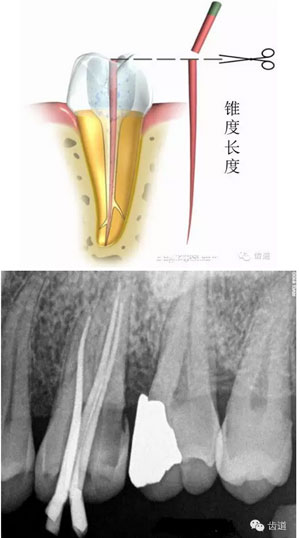

試尖,使其達到工作長度,修整超出根尖孔的多余牙膠尖。選擇合適的牙膠主尖,距根尖0.5-1mm處卡住即可;或者選擇預備時最后一支銼相同型號的牙膠尖,尖端需剪去0.5mm。

根據(jù)根管大小選擇匹配攜熱加壓頭,攜熱加壓頭尖部據(jù)根尖5mm左右即可,用橡膠定位圈定位。同理,選擇合適的垂直加壓器